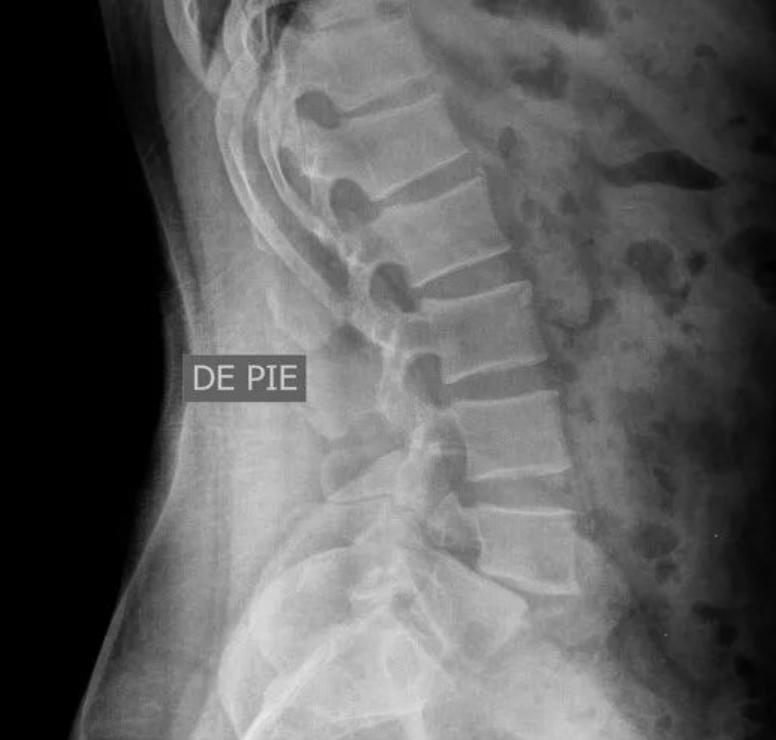

辑:腰4椎弓峡部裂,腰4椎体向前II度滑脱。

:腰4椎体向前滑脱达到了III度。

:腰4椎体向前滑脱,达到了III度。